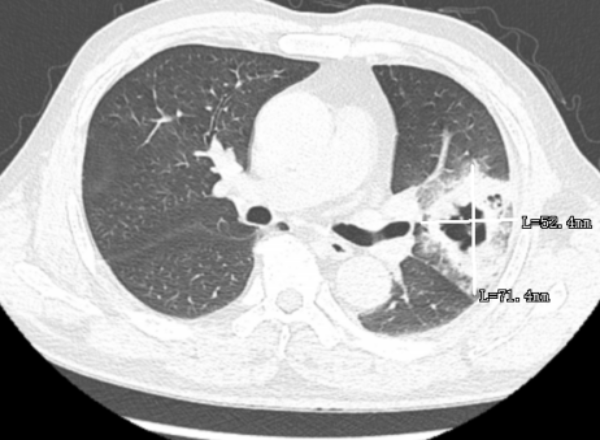

近日,中文博彩平台一位60岁的袁先生因发烧、胸痛、咳嗽且持续一周之久,到惠州市中心人民医院中文博彩平台分院(中文博彩平台人民医院)呼吸与危重症医学科门诊就诊,医生给患者开了一个CT检查,检查结果出来后,发现患者的肺部出现了一个6cm的病灶,因为患者持续发烧且温度不降,医生用药后效果不明显,于是给患者做了进一步的气管镜和病原体靶向测序的检查。

通过气管镜检查,发现患者的肺部中有许多脓痰,气管镜协助将脓痰吸引干净,并将脓痰送检病原体靶向测序,发现患者存在两种链球菌的感染,最终医生根据病原体靶向测序的结果进行针对性用药,患者便好转了很多,后续的CT检查中可以看到,6cm的病灶已缩小到2cm不到。

▲治疗前